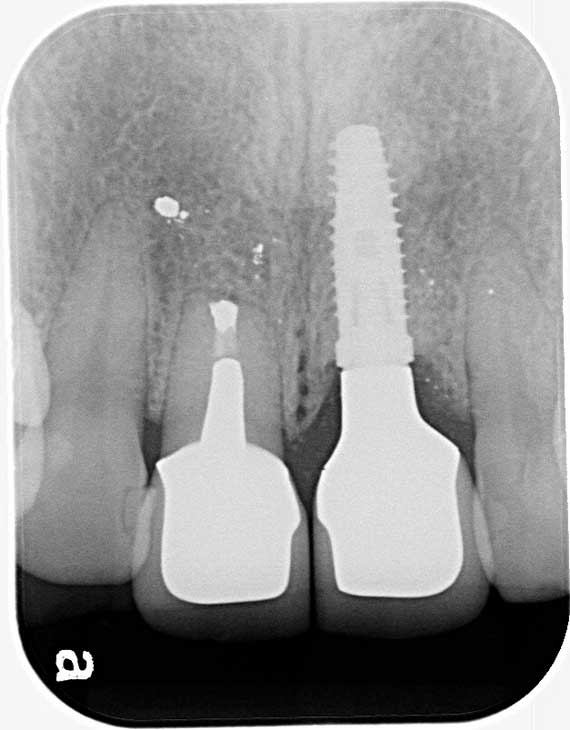

少し歯周病が進んでいたため、衛生士による歯周治療を進めながら、かみ合わせもチェック。その後、左前歯にインプラントを1本埋入し、右側とあわせて2本の前歯について、審美性の高いかぶせ物であるオールセラミッククラウンで補綴治療を行いました。

他院で抜歯した左前歯の骨の状態が良くなかったため、まず骨造成を行い、その後インプラントを1本植立しました。

インプラント植立した左前歯と一緒に右前歯にもかぶせ物治療を施し、3~4か月仮歯を装着して頂きながら、2本のバランスや対合する歯とのかみ合わせ、また色や形の調整を丁寧に行いました。